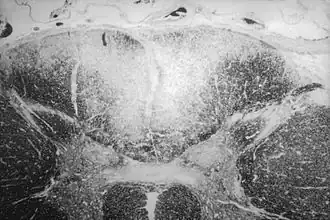

Прогресси́вный парали́ч, паралити́ческая деме́нция, паралити́ческое слабоу́мие или боле́знь Бе́йля — психоорганическое заболевание сифилитического происхождения, характеризующееся прогредиентным нарушением психической деятельности с формированием стойкого дефекта вплоть до деменции в сочетании с неврологическими и соматическими расстройствами. Впервые был описан французским психиатром А. Л. Бейлем в 1822 году[1]:26. Термин «прогрессивный паралич» предложен Delane. Впервые возможность сифилитического поражения мозговых оболочек и вещества головного мозга была выявлена Lalleman’ом в 1834 году при вскрытии умершего от сифилиса больного. Доказательством сифилитической природы болезни явилось обнаружение бледной трепонемы в коре мозга больных прогрессивным параличом Пятницким в 1911 году и американским учёным японского происхождения Х. Ногути в 1913 году. Прогрессивный паралич возникает с пиком заболеваемости в 10—12 лет после инфицирования у 1—5 % заболевших сифилисом[1]:398, поэтому в зрелом возрасте (30—50 лет) ≈ вдвое чаще у мужчин, и протекает более злокачественно, чем сифилис мозга, приводя к тяжёлым малообратимым последствиям.

При нейросифилисе выделяются прогрессивный паралич (при первичном поражении головного мозга) и сифилис мозга (при первичном поражении сосудов и оболочек мозга) в качестве отдельных нозоологических форм[1]:394. Прогрессивный паралич и сифилис мозга отличаются по клинической картине, по времени начала заболевания, а также по характеру и локализации патологического процесса[1]:394.